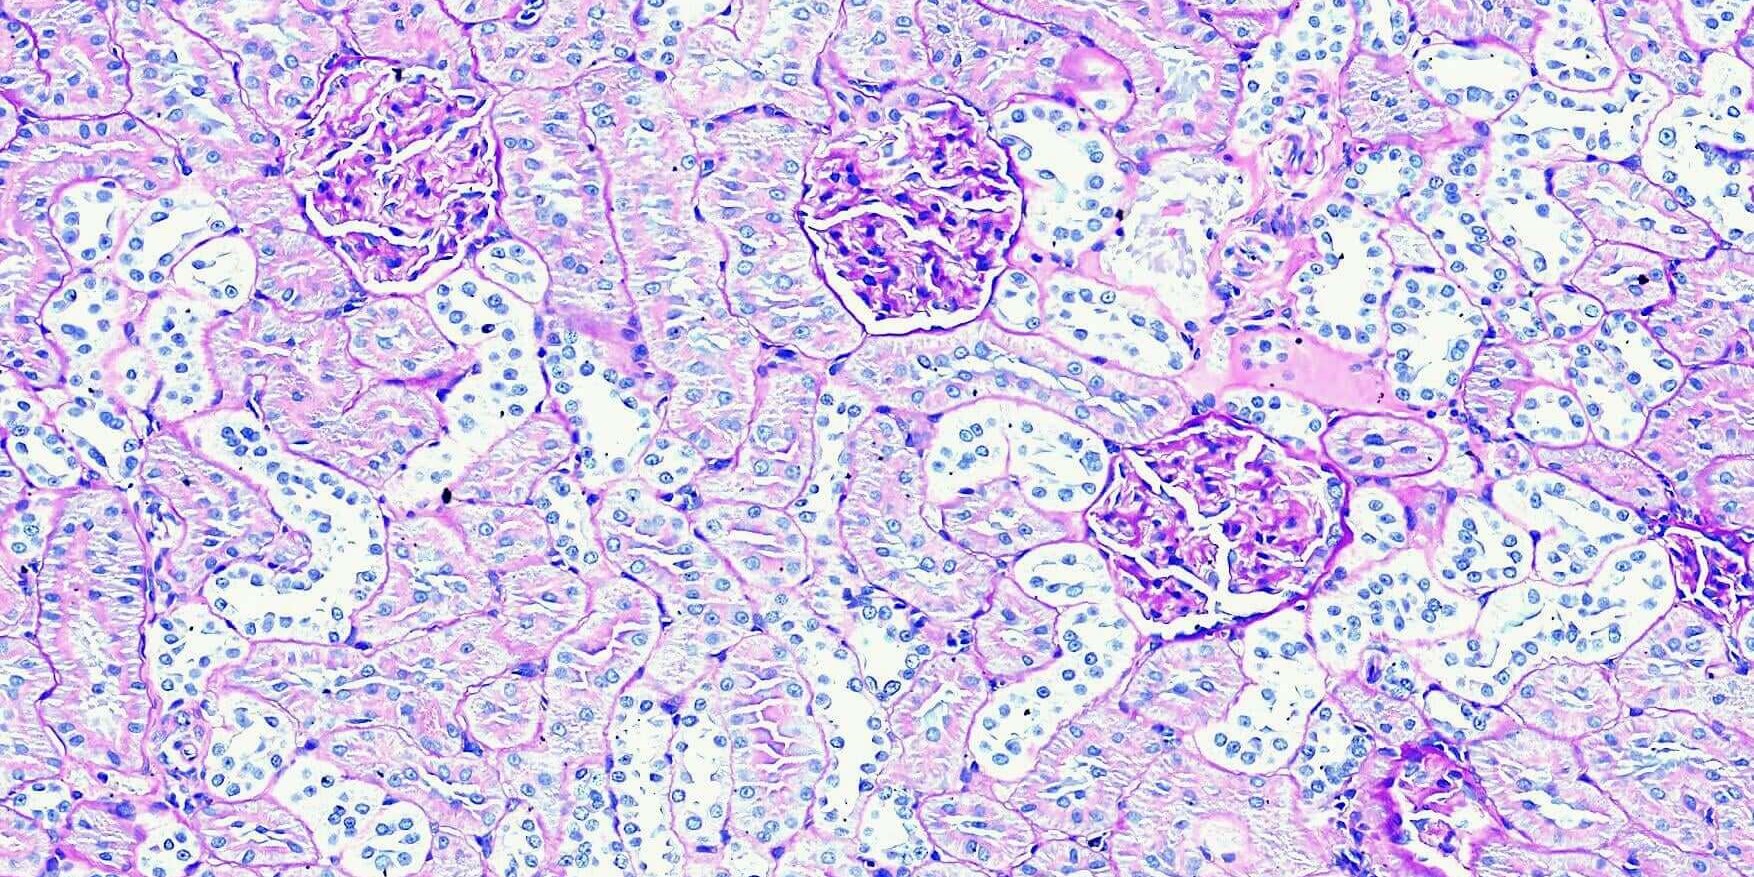

PAS染色主要用於標示組織中的醣類或醣蛋白,於腎臟常用於觀察基底膜(basement membrane)。在有慢性腎損傷,數常見如糖尿病時,常可見基底膜的增厚,於絲球體及鮑氏囊腔即可見大量PAS陽性組織表現。

立众病理實驗室獨家代理的 Biotna PAS 染色套組,能有效且清晰的呈現腎臟基底膜及其它陽性組織,不論配合蘇木紫(hematoxylin)或淺綠(light green)做為背景染色,都可以有漂亮的染色結果。